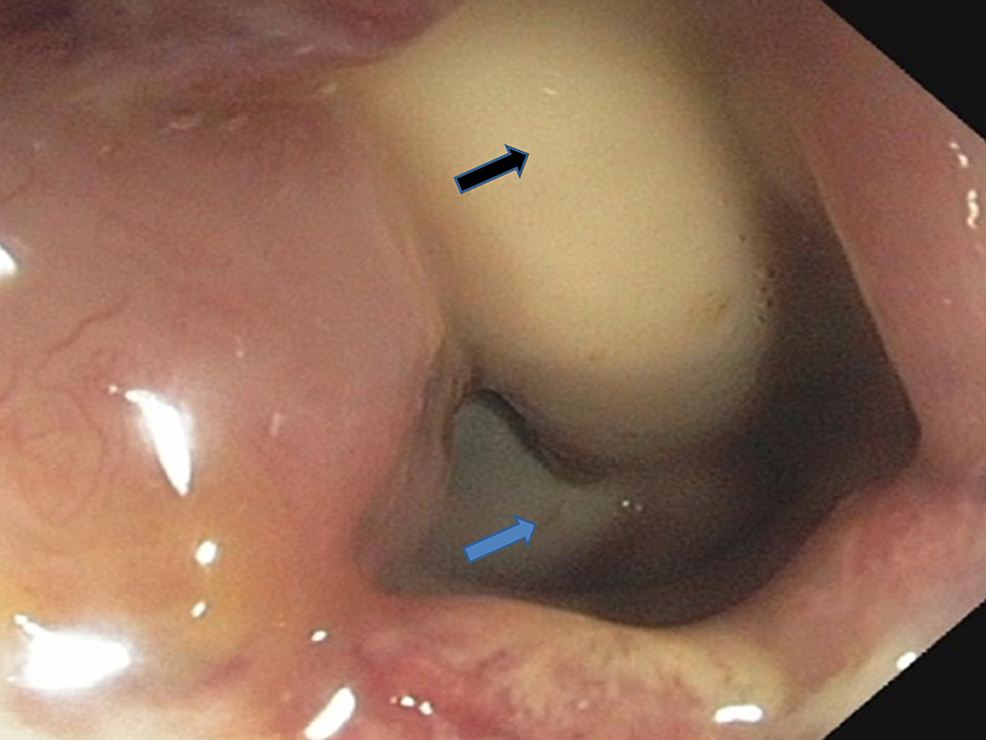

A colonoscopy was performed and revealed a Foley's catheter in the rectum (Figures 2-3). A rectal biopsy was not obtained, as, grossly, there was no evidence of malignancy, infectious process, or inflammatory process.